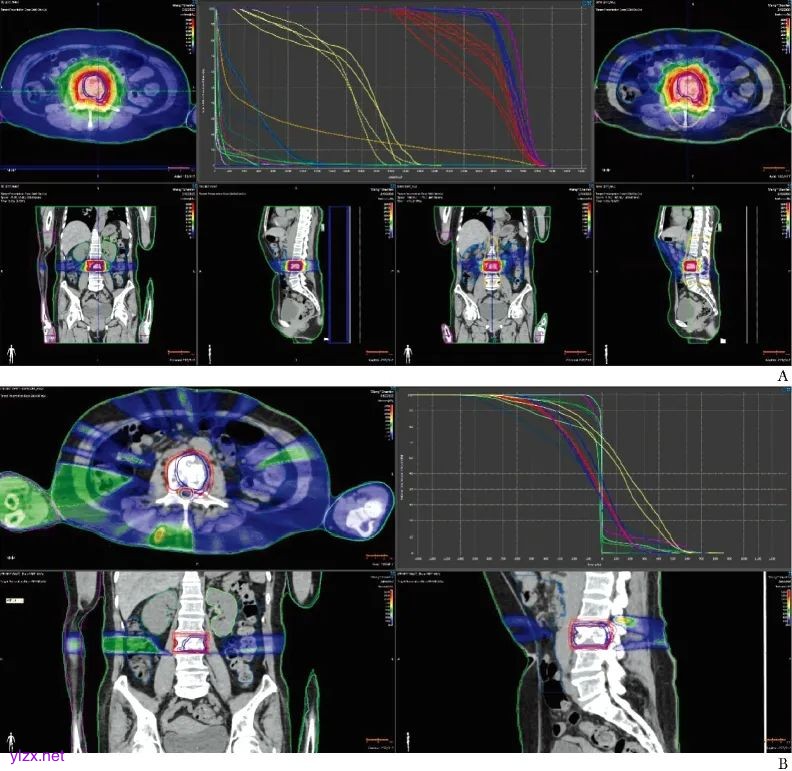

两例患者CyberKnife技术与调强适形放疗计划剂量对比见图1和图2。

图2 患者2采用CyberKnife与普通调强适形放疗计划剂量比较

A.CyberKnife(右)与普通调强适形放疗计划(左)剂量分布; B. CyberKnife与普通调强适形放疗计划剂量差异

两种计划剂量图对比结果显示,CyberKnife技术在不扩大PTV的前提下,可提供更高剂量照射,减少危及器官照射剂量,从而最大限度地减轻组织或器官损伤,实现更加精准的肿瘤放疗,具有显著的剂量学优势。